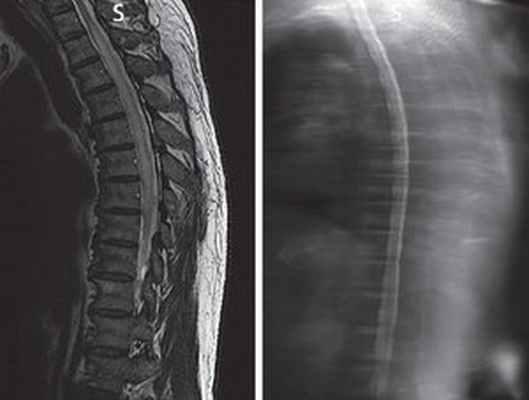

(Слева) Сагиттальный срез, Т1-ВИ: множественные метастатические очаги в телах шейных и верхнегрудных позвонков с признаками перестройки костного мозга после проведенной лучевой терапии. Спинной мозг несколько утолщен.

(Справа) Сагиттальный срез, Т2-ВИ: продольно распространенное усиление сигнала паренхимы спинного мозга и некоторое его утолщение. Подобная картина отека не является специфической, поэтому всегда необходимо исключить метастатическое поражение спинного мозга и пострадиационные изменения.

(Слева) Сагиттальный срез, Т1-ВИ с КУ: типичная картина па-ранеопластической миелопатии с фокальным симметричным контрастным усилением сигнала центральных столбов спинного мозга. Подобной симметричной картины при метастатическом поражении или пострадиационных изменениях не будет.

(Справа) Сагиттальный срез, Т1-ВИ с КУ, пациент с фокальным метастатическим поражением спинного мозга: строго ограниченное контрастирование очага опухоли в сочетании с продольно распространенными паранеопластическими изменениями спинного мозга.